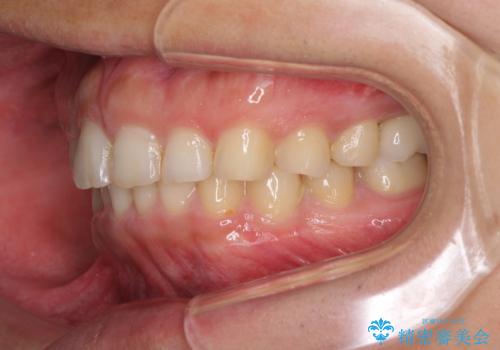

矯正治療とインプラント治療を同じ歯科医師が担当することで、通常見られるような複数医院を行き来する煩雑さや、複数担当医の見解の違いによる治療の遅滞といった煩わしさは一切なく、スムーズに治療を進めることができました。

安定して咬めるようになり、患者様には大変満足していただきました。